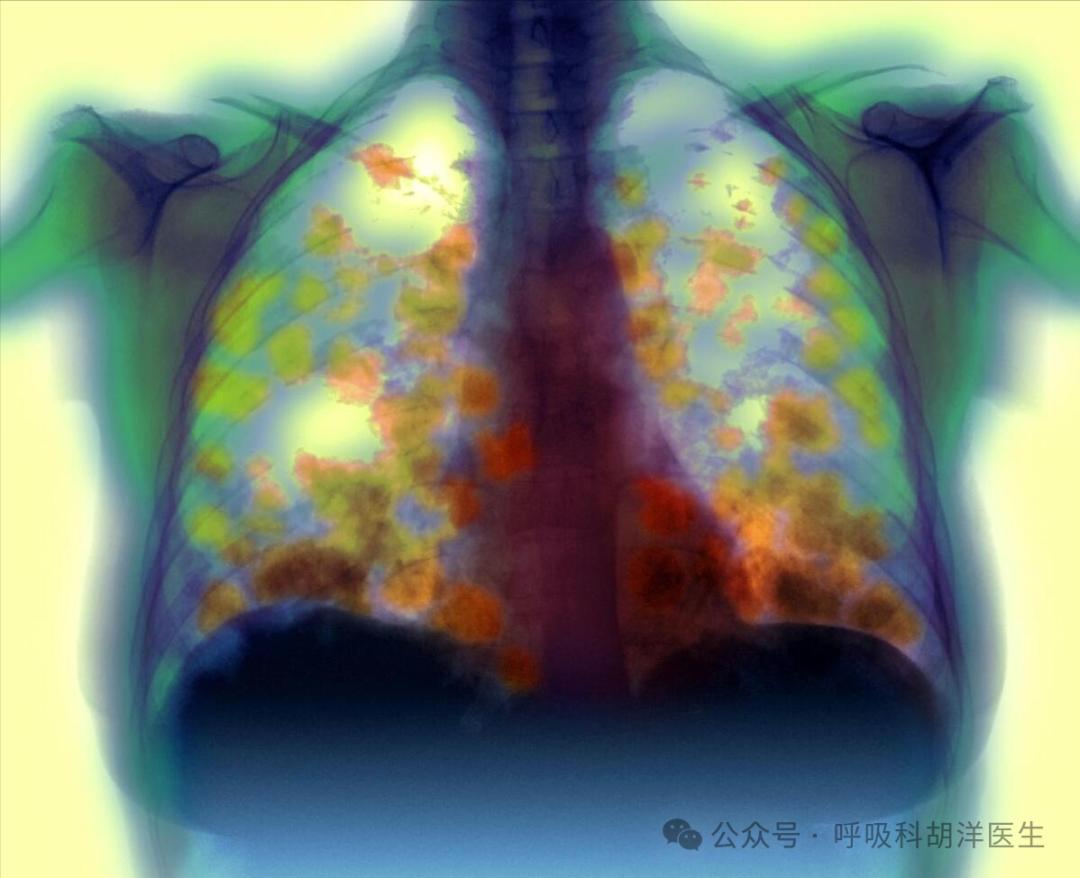

大多数肺癌在早期可以通过手术治愈,在晚期可以通过靶向、化疗、免疫或放疗延长寿命。然而,有些患者由于各种原因无法使用任何方法,尤其是一些早期肺癌患者,诊断后无法进行手术治疗。可惜是什么问题让他们无法治疗?

最近有个病人是我的亲戚。他80岁了,被诊断为早期肺癌。他的家人非常活跃,想做手术治疗。他希望他能再活十年。当地医生告诉他不可能做手术,他不相信。于是他给我发了一份报告。从CT和病理检查结果来看,确实是早期肺癌,直径不到2厘米。然而,当我看到肺功能时,我皱起了眉头。FEV1只有0.86。他说好,基本上只能躺着或坐着不动,一动就喘不过气来。

毕竟我劝他放弃。患者不仅肺功能差,还有其他基础疾病,甚至呼吸衰竭和心力衰竭。手术台可能可以上去,但是下不去的概率很大。估计麻醉也过不去。问我能不能保守治疗?我说可以配靶向药,也可以吃靶向药。如果靶向药配不上,只能用中药调理。家人听说后去做基因检测。